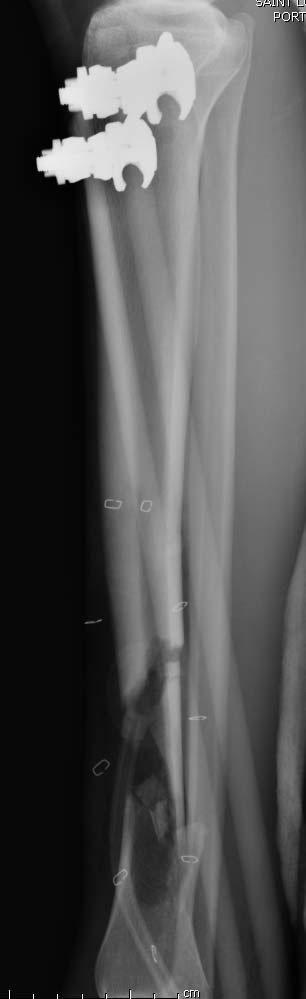

Здравствуйте уважаемые коллеги, прошу поделиться опытом лечения подобных повреждений-осложнений. Пациент Б. 40 лет, поступил в клинику 6.11.19 с огнестрельным переломом н/3 правого бедра и повреждением магистральных сосудов. Произведена ПХО ран, стабилизация перелома(с укорочением на 5 см.)стержневым АВФ, шов сосудов конец в конец. К сожалению, неверная выжидательная тактика привела к нагноению раны(Kl.pneumoniae).22.11.19 Этапная ХО раны, перемонтаж АВФ по типу-гибрид, удаление девитализированных костных фрагментов, депонирование дефекта бусами-спейсерами (амикацин-ванкомицин),VAC, Тигацил 100 мг.сут.26.11, 29.11, 3.12-этапные ХО с заменой бус и VAC,бак.посевы(возбудитель присутствует) . Макроскопически рана очистилась, гранулирует, однако имеется воспаление вокруг стержней. t. тела-в пределах нормы, лейкоциты снизились с 9,5 до 6.3, СОЭ с 62 до 31,СРБ с 98 до 49,гемогробин-98.Какую тактику применить на данном этапе?1 Masquelet с конверсией на гвоздь(пластину) с антибиотиком.2Аппаратное лечение с транспортом кости.3Другие возможные варианты.Заранее благодарю за помощь.

А воспаление вокруг стержней происходит из-за того, что на бедре мягкие ткани более мобильные, и возле нестабильных стержней образуется реактивное воспаление. Если не лечить, тогда воспаление может перейти в глубокие слои, а в данном случае (fat necrosis), т.е. локальный некроз, который лечится обработкой и созданием стабильности.

В данное время нет подтверждающих признаков распространения инфекции по медуллярному каналу, а также отсутствует данные, что повторная хирургическая обработка может повлиять на процесс образования тромбоза.